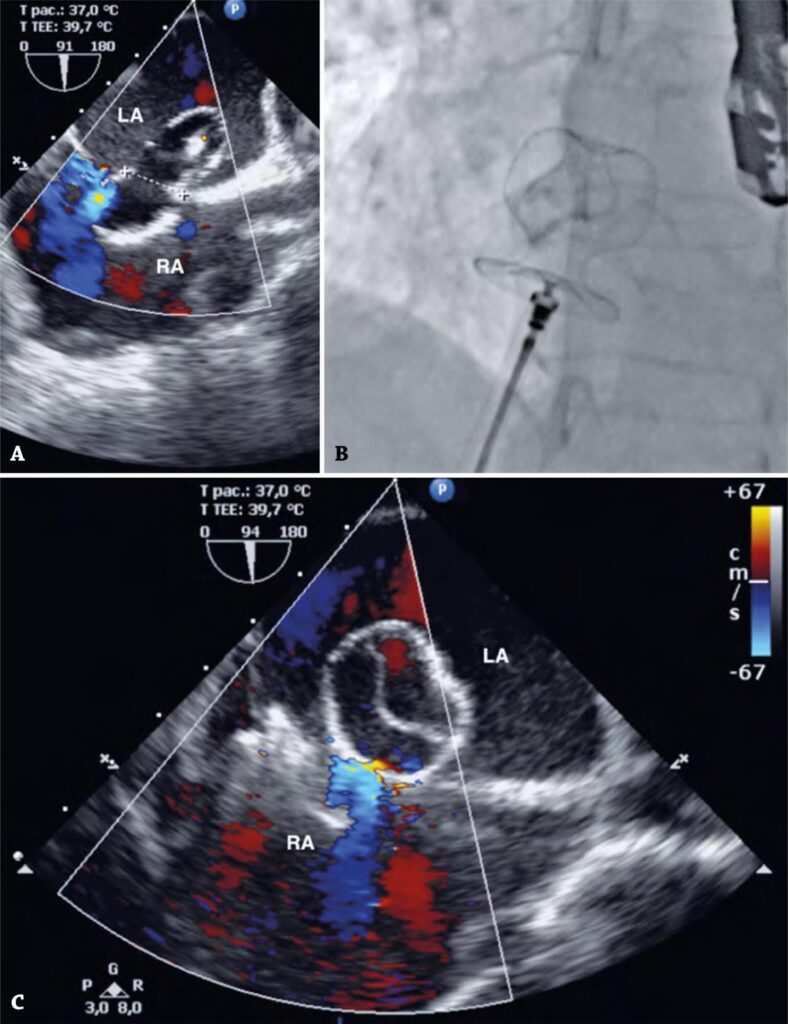

A 47-year-old woman was referred for transcatheter closure of a secundum atrial septal defect (ASD). Vascular access was obtained via the right femoral vein and 16-mm ASD diameter was determined using balloon and the stop-flow sizing technique ().

Figure 1

(A) Transesophageal echocardiography image of 16-mm ASD diameter determined using a balloon and stop-flow sizing technique. (B) The 16-mm CeraFlex™ ASD Occluder showing the tulip shape of the left atrium disc after removal from the 12-F delivery catheter. Fluoroscopic images in two views. (C) Transesophageal echocardiography image.